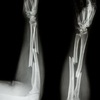

Fratura em galho verde + deformidade plástica